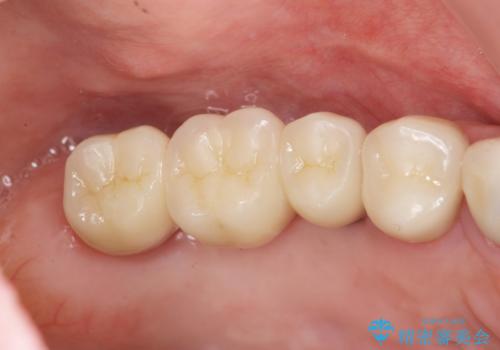

銀歯がセラミッククラウンとなり見た目は美しくなりましたが、審美性だけでなく清掃性も向上し、歯ぐきの状態も良好で、歯周病の再発なく経過しています。